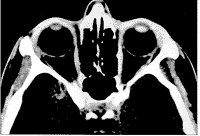

眼眶计算机X线断层照相扫描无异常